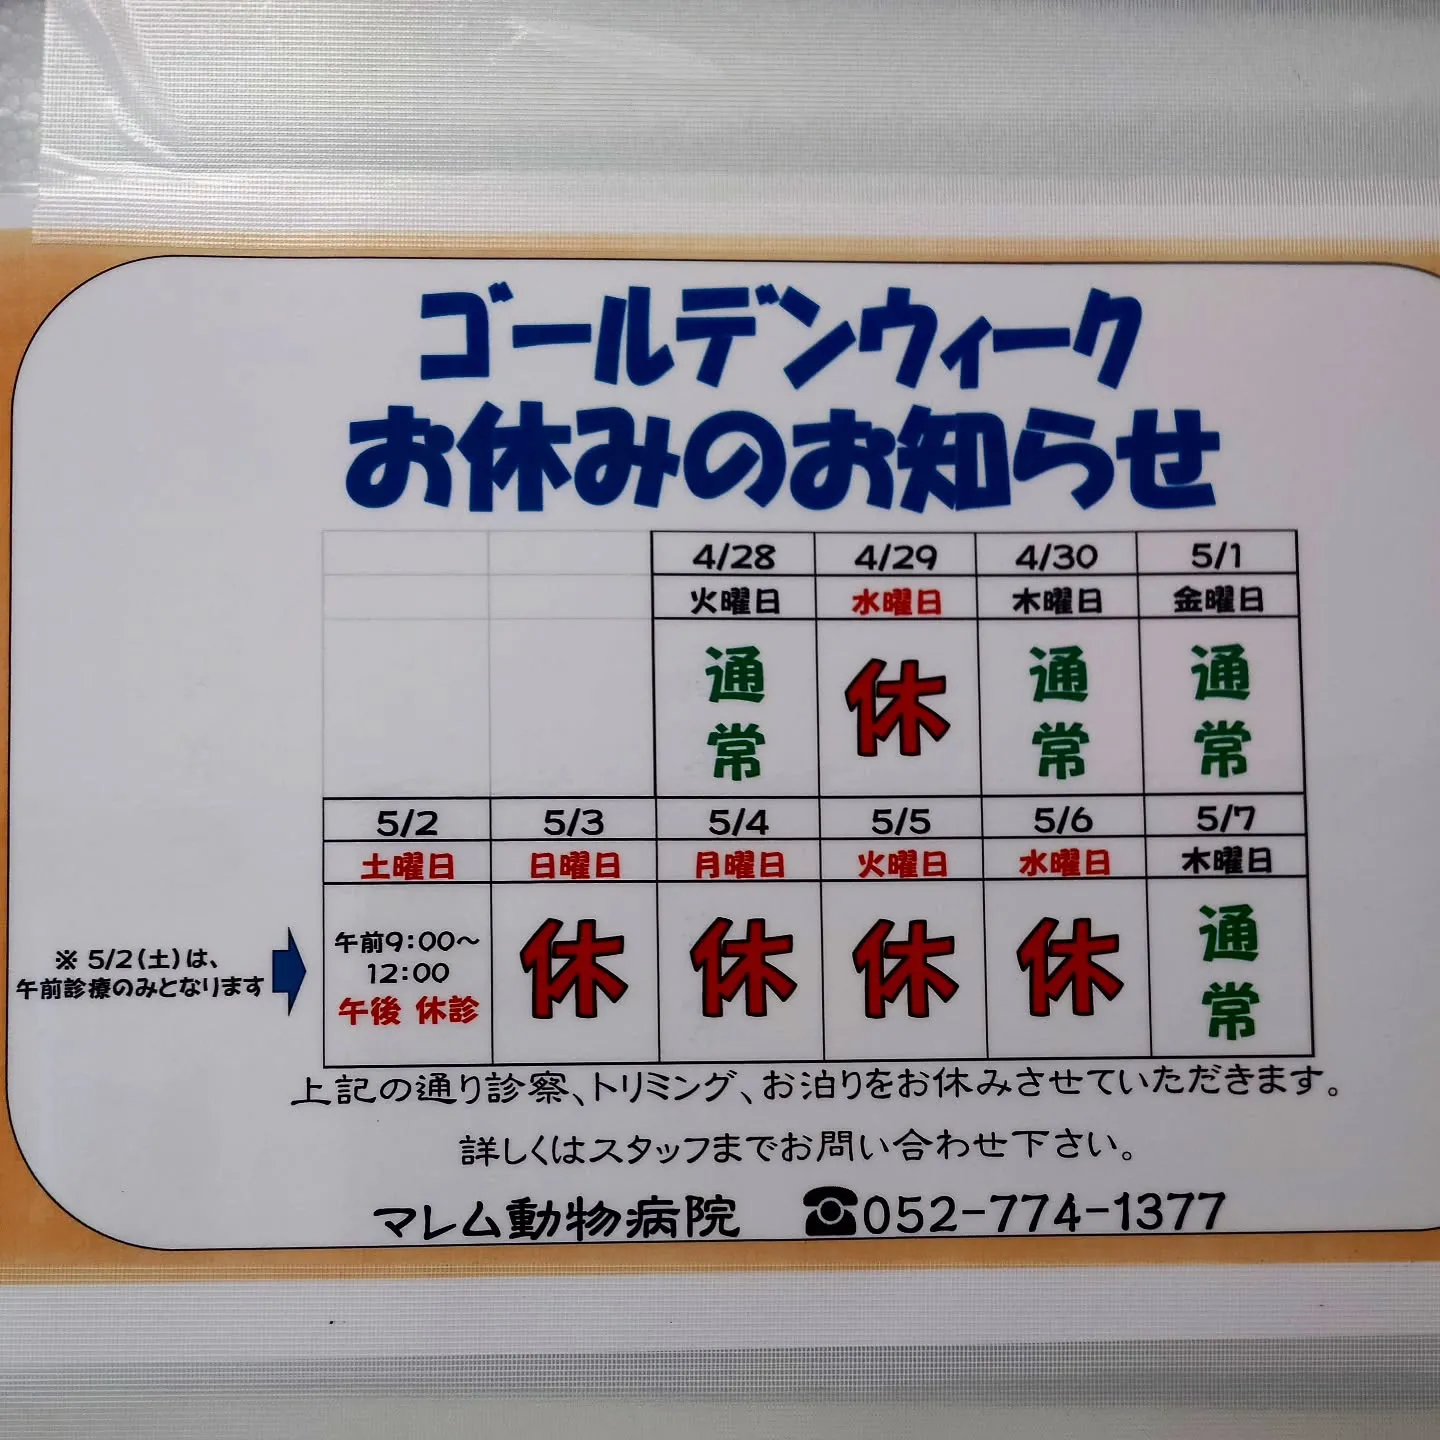

普段の診察では「オモチャを食べてしまった」なんて話はよくあることです。

レントゲン撮影では骨、小石や金属はわかりやすいですが、ぬいぐるみやティッシュ、プラスチック等はかなり特殊な条件でないとわかりません。

写真は、ぬいぐるみとプラスチックのドラえもんのレントゲンです。金属ねじははっきりとわかりますが、ドラえもんの形など細部はぼんやりしており、写りにくいです。

なるべく異物を飲み込ませないように気をつけてくださいね。

食欲不振、ぐったりや頻回嘔吐等の症状を確認したら当院までご連絡ください。

【失敗】私の想定よりもぬいぐるみドラえもんが写ってしまいました。